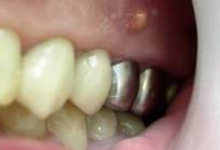

Киста зуба: фото